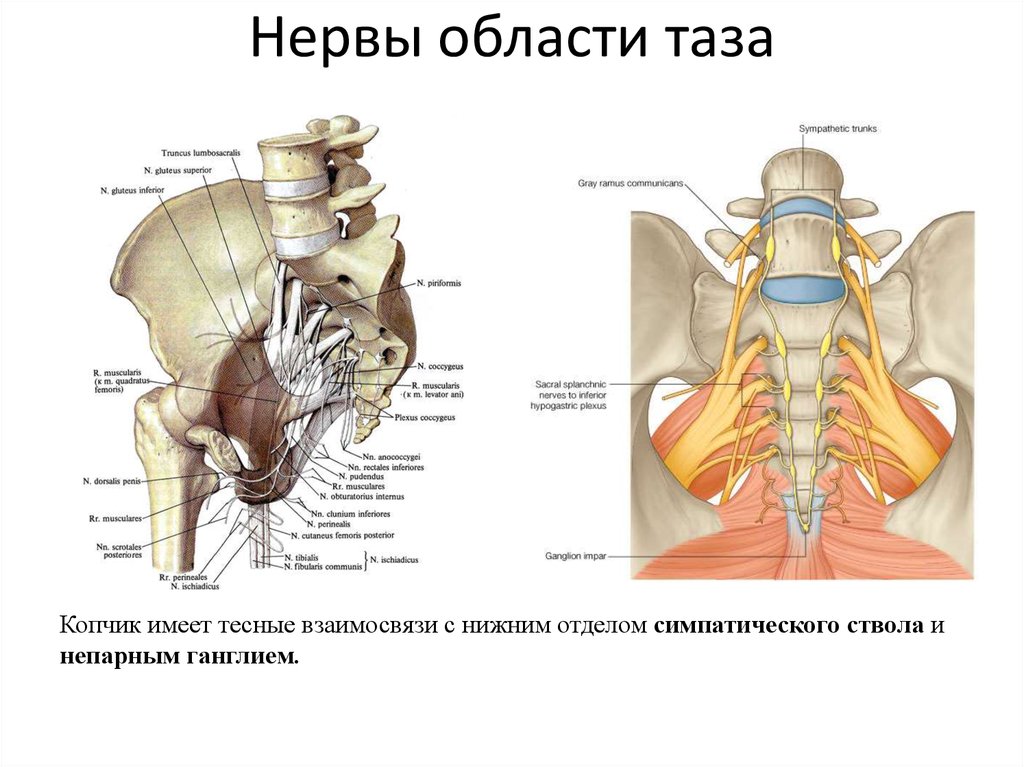

Анатомия малого таза: детальные схемы и изображения